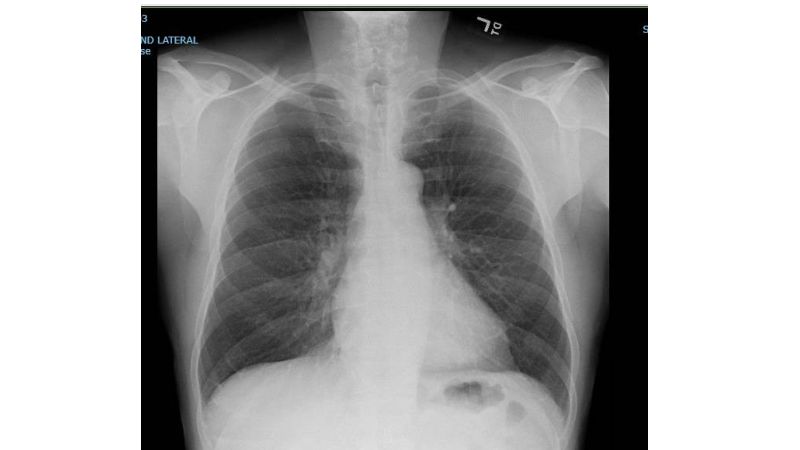

Explore the mystery of why there's no gas in the pleural space in this fascinating on-demand teaching session tailored for medical professionals. Learn about the different pressures at play like the atmospheric and pleural space pressures, as well as the role played by gases like O2, H2O, N2, and CO2 in the human body. This course aims to clarify the reasons behind the absence of gas in the pleural space under normal physiological conditions and discuss the scenarios that would allow gas to penetrate this area. Dive deeper into this topic and come out with an understanding that may be very beneficial in managing conditions like pneumothorax. This still is surely a perfect addition to your medical knowledge arsenal.

Why is there no gas in the pleural space? • Atmospheric pressure: 760 mmHg • Pleural Space Pressure: 757 mmHg • Gases in humans: • O2 = 40 mmHg • H2O = 47 mmHg • N2 = 573 mmHg • CO2 = 46 mmHg • TOTAL:706 mmHg– meaning, gases would moveintohere if thepleural pressureis less than 706 mmHg(which does notoccurphysiologically)Why is there no gas in the pleural space? • Three ways gas would be in pleural space: • Connectionbetweenpleural spaceand alveoli • Connectionbetweenatmosphereand pleural space • Gas forming organisms presentHowdo we TREA T pneumothorax? • Atmospheric pressure: 760 mmHg • Pleural Space Pressure: 757 mmHg • Gases in humans: • O2 = 40 mmHg • H2O = 47 mmHg • N2 = 573 mmHg • CO2 = 46 mmHg • pressureis less than 706 mmHg(which does notoccurphysiologically)Howdo we TREA T pneumothorax? • Atmospheric pressure: 760 mmHg • Pleural Space Pressure: 757 mmHg • Gases in humans: • O2 = 40 mmHg • H2O = 47 mmHg • N2 = 573 mmHg • CO2 = 46 mmHg • TOTAL:173 mmHg